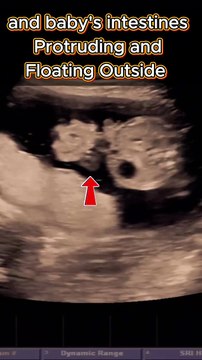

Kashif Ultrasound

4.3wks Early Pregnancy Ultrasound - Why it is needed